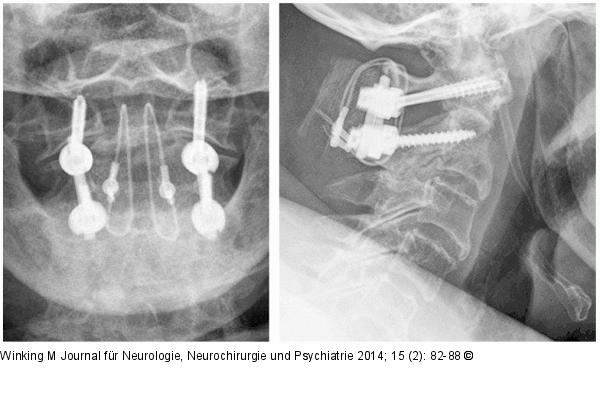

Abbildung 7: Rheumatische Wirbelsäule Röntgenaufnahmen im anterior-posterioren und seitlichen Strahlengang nach dorsaler Verschraubung von HWK 1 mit 2 durch Schrauben-Stab-System und Beckenkammspaninterposition mit Titan-Kabelcerclage gesichert. |

Röntgenaufnahmen im anterior-posterioren und seitlichen Strahlengang nach dorsaler Verschraubung von HWK 1 mit 2 durch Schrauben-Stab-System und Beckenkammspaninterposition mit Titan-Kabelcerclage gesichert. |